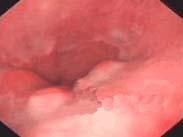

Barrett食管是指食管下段的復層鱗狀上皮被單層柱狀上皮所替換的一種病理現象。本身可無特殊癥狀,當呈現食管炎、潰瘍、癌變時才會出現相應的反流癥狀,部分Barrett上皮易發生癌變。